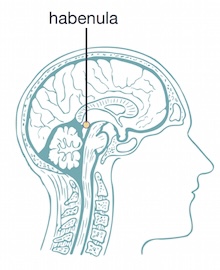

وجد الباحثون أن هذه الخلايا العصبية تتواصل مع منطقتين مختلفتين في الدماغ: منطقة الهيبينولا «العِنان» الجانبية[6] ، وهي منطقة دماغية رئيسة في الفيزيولوجيا المرضية pathophysiology «انظر[7] للاكتئاب، والمنطقة السقيفية البطنية ventral tegmental «انظر[8] ، والمعروفة بالدور الرئيس الذي تلعبه في التحفيز والمكافأة والإدمان.

حللت هذه الدراسة الحديثة الخلايا العصبية الغلوتاماتية الجانبية تحليلًا منهجيًا. وجد الباحثون أنه عندما تُغذى الفئران، تصبح الخلايا العصبية في منطقة الهيبينولا الجانبية أكثر استجابة من تلك الموجودة في المنطقة السقيفية البطنية، مما يوحي بأن هذه الخلايا العصبية قد تلعب دورًا أكبر في التأثير في الأكل.